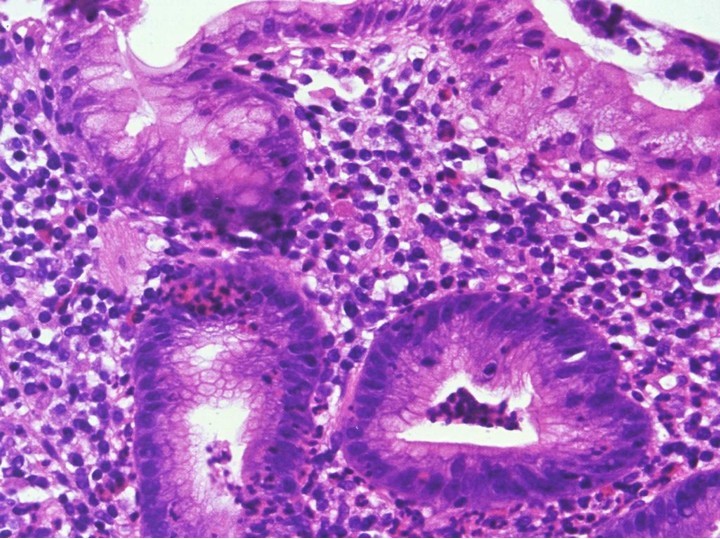

27 year-old male has a history of longstanding abdominal pain and diarrhea. What is the histologic finding below indicative of?

Crohn Disease non-caseating granuloma